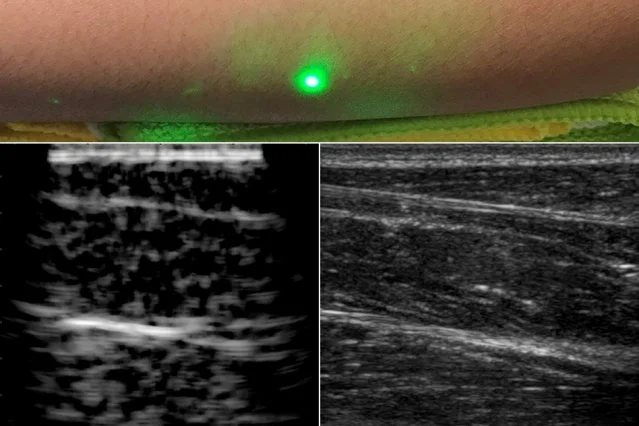

Laser Ultrasound

We demonstrated the first laser ultrasound (LUS) image on a human subject as part of my Doctoral Research at MIT. We successfully produced 2D and 3D images on phantoms, animal tissue, and human subjects. See more in the linked publication.